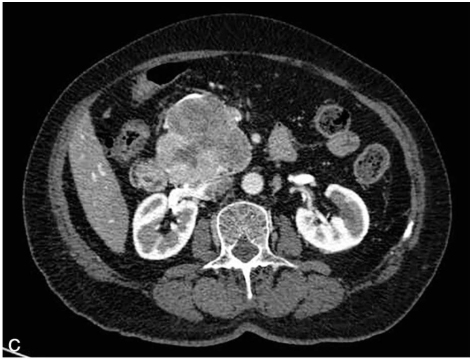

胰腺增强MRI(图2)示胰头钩突部异常信号影,囊性成分为主,T2WI呈高信号为主,局部见条片状低信号影,T1WI呈不均匀低信号,DWI呈稍高信号;病灶边缘分叶状,内可见多发细密蜂窝状分隔,并见瘢痕样改变,增强扫描病灶边缘及分隔呈明显强化。

图2 胰腺增强MRI

A.T1WI;B.T2WI;C.DWI;D.动脉期;E.静脉期;F.冠状面平衡期。